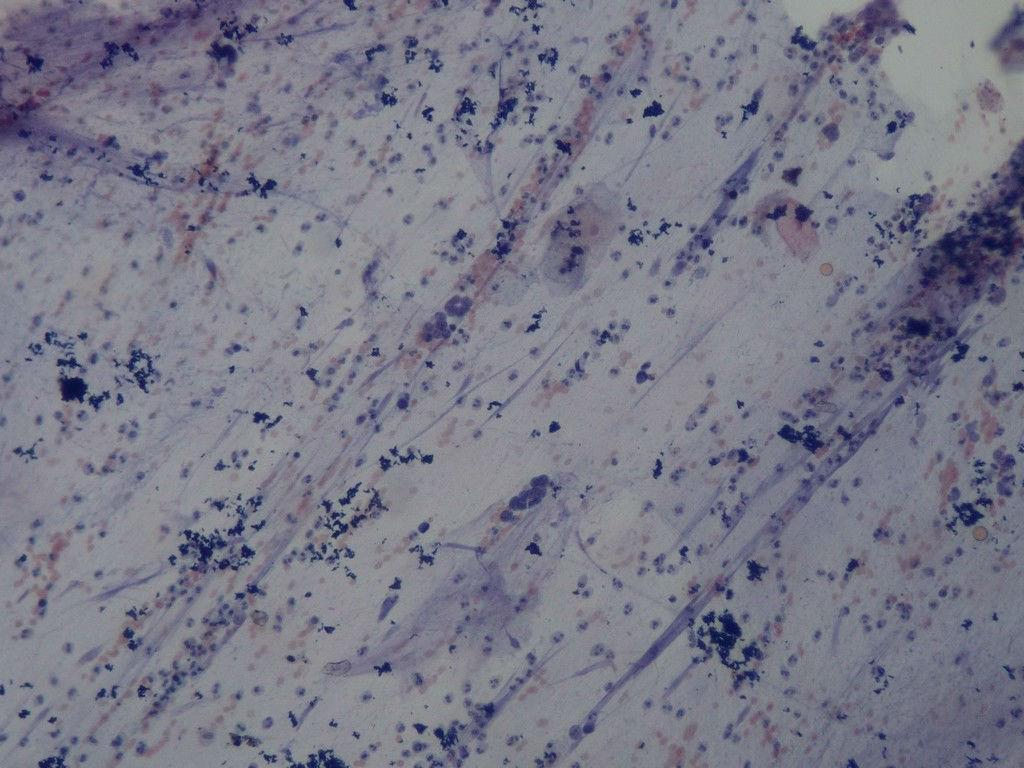

痰涂片

• 痰涂片图1

涂片内见癌细胞,考虑小细胞癌。

癌,小细胞癌?

少量不能下诊断的细胞,部分裸核,免疫母副免疫母可能!未见明显恶性肿瘤细胞,如临床怀疑,继续送检并多涂片~~~

癌细胞 小细胞癌

具有小细胞癌的特点